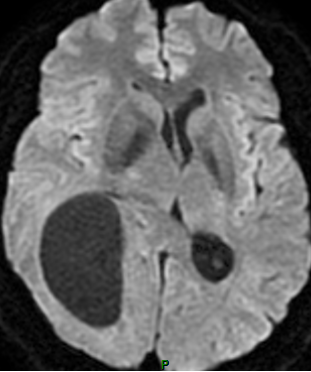

患者中年男性,因“颈部发紧、活动受限伴头晕近半月”入院。PE:NS(-)。头颅MRI平扫+增强检查示右颞枕叶椭圆形囊性肿物,边界清楚,信号均匀,病变周围可见片状水肿,中线结构略向左偏;增强扫描囊壁不规则环状强化(图1)。